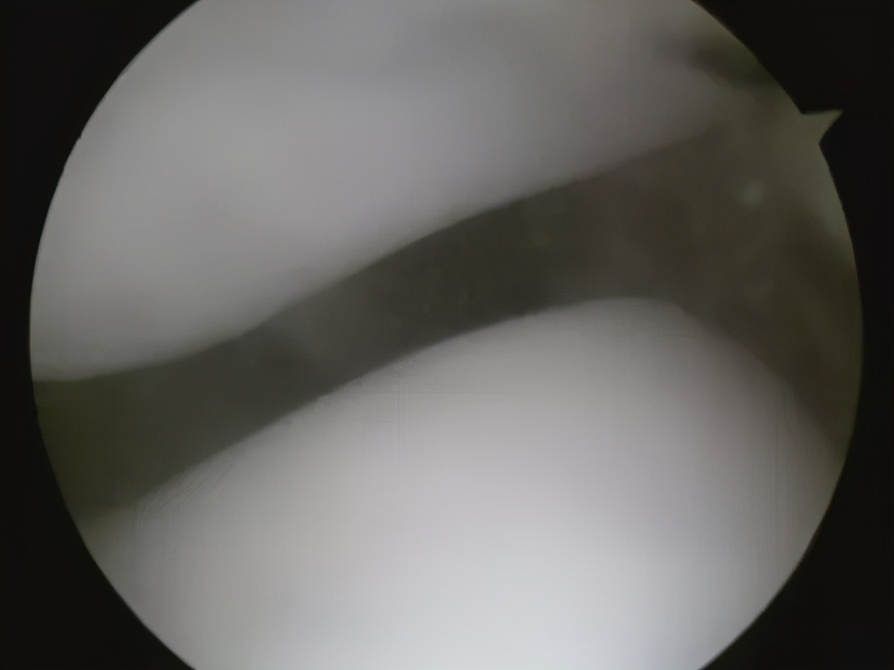

正常的髌股关节

饱经沧桑的髌股关节